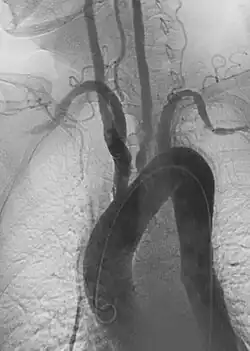

Angiography: Sometimes referred to as traditional angiography, catheter angiography or digital subtraction angiography (DSA). A small needle is inserted into a blood vessel, then exchanged for a catheter over a wire. The catheter is directed at the vessel to be studied, and contrast is directly injected to evaluate the lumen under video X-ray. This is an older technique than modern CT angiography or MR angiography, but provides unique advantages. With a catheter in place, provocative maneuvers can be performed such as breath holds or instillation of vasodilators, to evaluate a patient's blood flow dynamically. This can reproduce symptoms and identify functional abnormalities in a vessel that a static CT or MR imaging cannot.[80][81] Angiography provides the basis for all endovascular therapy.

Takayasu arteritis angiography